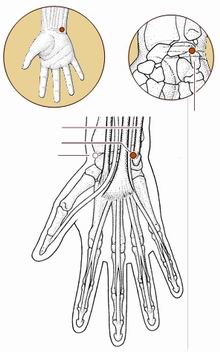

神门穴

经穴名。出《针灸甲乙经》。《难经·六十六难》名兑骨。别名兑中、中都、锐中。属手少阴心经。输(土)、原穴。在腕部,腕掌侧横纹尺侧端,尺侧腕屈肌腱的桡侧凹陷处。布有前臂内侧皮神经,尺神经及尺动脉。主治心痛心烦,惊悸怔忡,健忘失眠,癫狂,痫症,目黄,失音,喉痹,胁痛,腕关节痛等。直刺0.3-0.5寸。艾条灸5-10分钟。